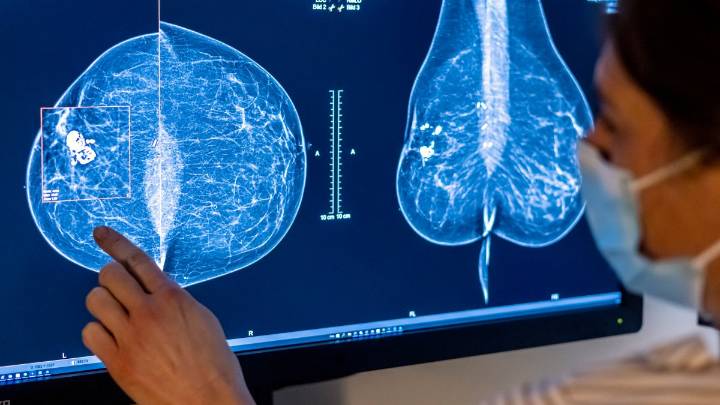

Routine mammograms are the mainstay of breast cancer screening . But, with a new type of analysis powered by artificial intelligence, doctors may be able to also predict whether or not you'll develop breast cancer in the next few years.

The technology, called Clairity Breast , is the first of its kind to receive authorization from the Food and Drug Administration. It's just starting to appear in some hospitals in the U.S. And, experts say, when interpreted correctly, it can be an important tool in identifying those with a higher risk for breast cancer.

Using images from a mammogram, the technology generates a risk score, which is the probability that someone will develop breast cancer in the next five years.